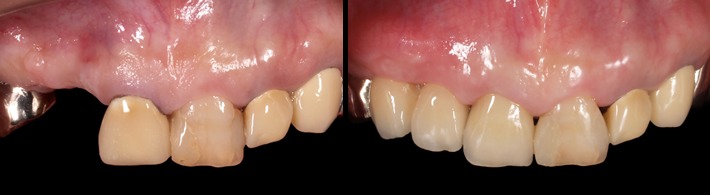

初診時

ファイナルレストレーション